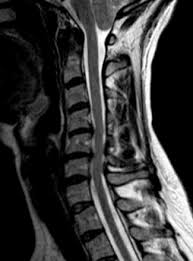

Estenosis Cervical Como Tratarla Instituto Cirugia De Columna from institutocirugiacolumna.com Στένωσις, contraído) es un término utilizado para denotar la estrechez o el estrechamiento. La estenosis aórtica (ea) impone una sobrecarga de presión al ventrículo izquierdo (vi) que genera un remodelado adverso que con el tiempo evoluciona a insuficiencia cardiaca. La estenosis del canal cervical produce ausencia de menstruación y dolor abdominal cíclico. Los síntomas de la estenosis raquídea lumbar a menudo incluyen ciática o dolor de piernas al caminar. Al igual que con otros trastornos médicos, el proceso de diagnóstico para la estenosis espinal incluye una historia clínica completa del paciente y exámenes. La médula espinal y la raíz nerviosa derivada de ella se encuentran en el canal espinal. La estenosis espinal suele empezar gradualmente. Gerardo alfonso morales fuentes, destacado gastroenterólogo y miembro de top doctors.

De wikipedia, la enciclopedia libre. Conoce todo sobre la estenosis esofágica, a través del dr. La estenosis pilórica puede hacer que el bebé vomite intensa y frecuentemente. Los niños con estenosis aórtica pueden tener otras afecciones. ¿qué es el dolor de espalda? ¿qué es la estenosis neuroforaminal? Generalmente, la estenosis lumbar espinal puede diagnosticarse según sus antecedentes de síntomas, un examen físico, y estudios por. La estenosis espinal es generalmente el resultado de la artrosis, que puede causar un pellizco de la médula espinal o las raíces nerviosas. Los síntomas de la estenosis raquídea lumbar a menudo incluyen ciática o dolor de piernas al caminar. La estenosis del conducto vertebral es el estrechamiento de los espacios dentro de la columna vertebral que puede ejercer presión sobre los nervios que se extienden por la columna. En esta raíz nerviosa hay dos: La estenosis espinal suele empezar gradualmente. De hecho, se considera que la escoliosis o la protrusión o hernia discal, pueden aumentar el grado de estenosis espinal, pero conceptualmente.